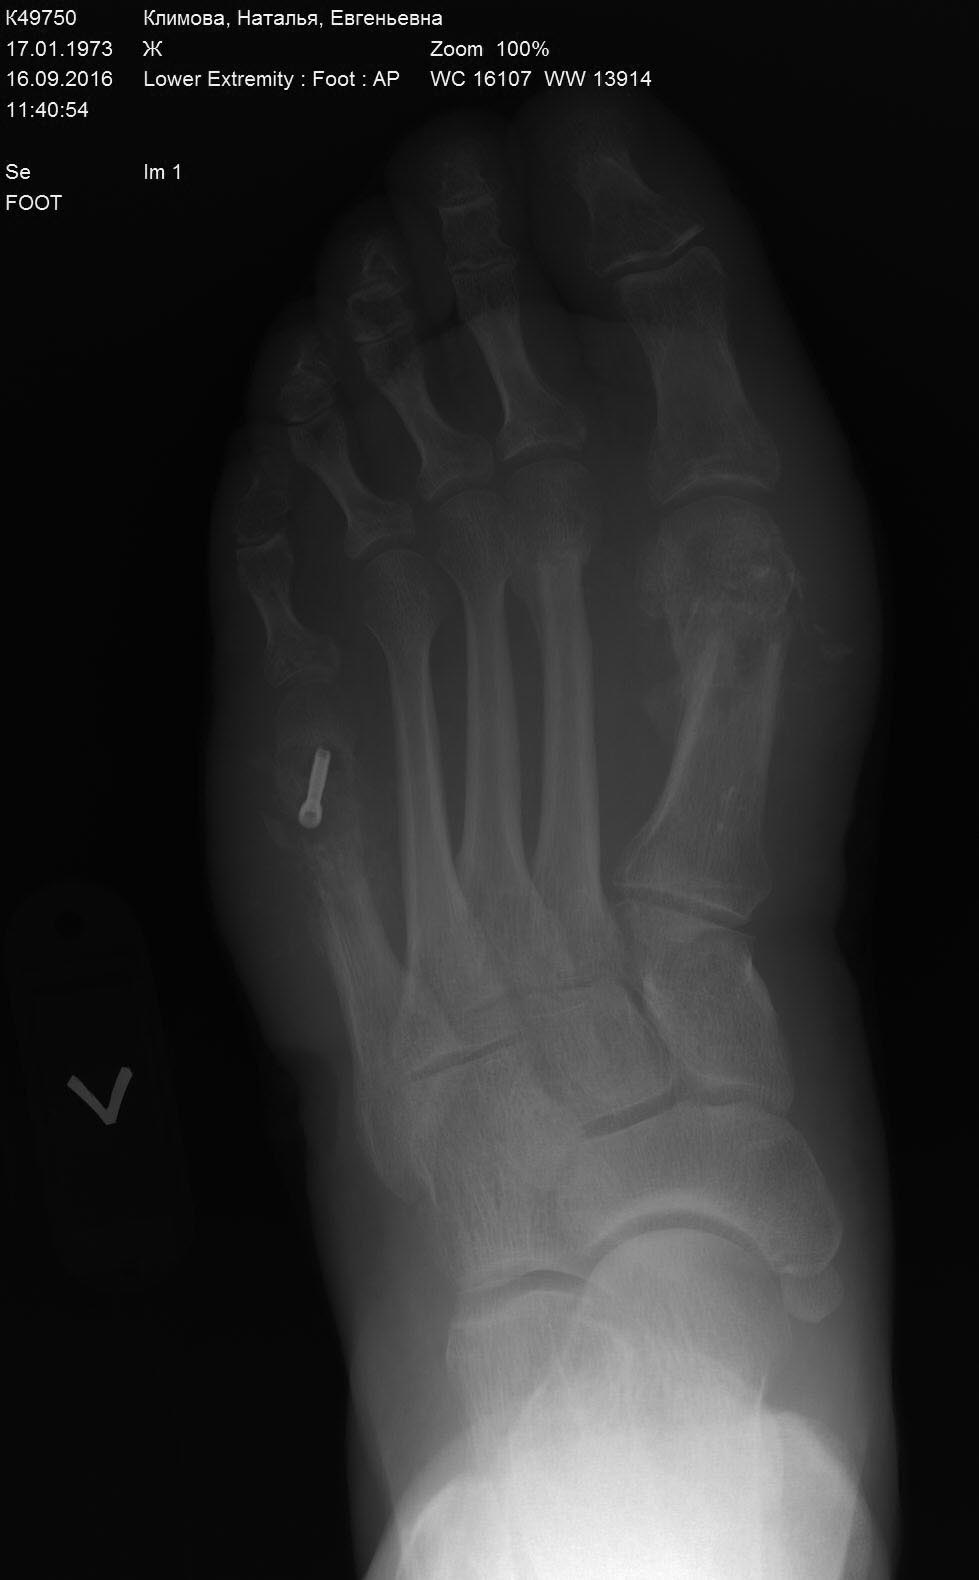

Пациентка 40 лет. Оперирована в июне 2016г- реконструктивная операция на

1-й плюсневой кости левой стопы по поводу вальгусной деформации 1-го

пальца и на 5-й плюсневой по поводу деформации Тейлора. В стационаре

после операции провела 5 дней, выписана в удовлетворительном состоянии

со спокойными п/о ранами. Через 6 недель у пациентки в области п/о рубца

в проекции 1-й плюсневой кости открывается свищ. Пациентка амбулаторно

перевязывается.

br>Через 8 недель на Р-контроле выявляется миграция винта в 1-й

плюсневой кости, который амбулаторно удален. Пациентка в этот момент

жалуется только на отечность переднего отдела стопы и отделяемого свища.

Лихорадку пациентка отрицает. В крови С-реактивный белок в норме,

лейкоцитарная формула тоже в пределах нормы. br>Через 10 недель

пациентка приносит Р-контроль где имеются отчетливые признаки резорбции

костной ткани в 1-й и 5-й плюсневых костях. br>Пациентка направлена на

оперативное лечение. 3 дня назад выполнена операция- секвестрэктомия 1-й

и 5-й плюсневой кости и установлена вакуум-система. В качестве

иммобилизации установлена гипсовая иммобилизация. На завтра планирую под

наркозом снова произвести промывание ран с заменой полиуретановых губок

и продолжить вакуум терапию. После вакуума планирую аппарат внеш-й

фик-ции и открыто вести раны. Это мой первый опыт в лечении остеомиелита